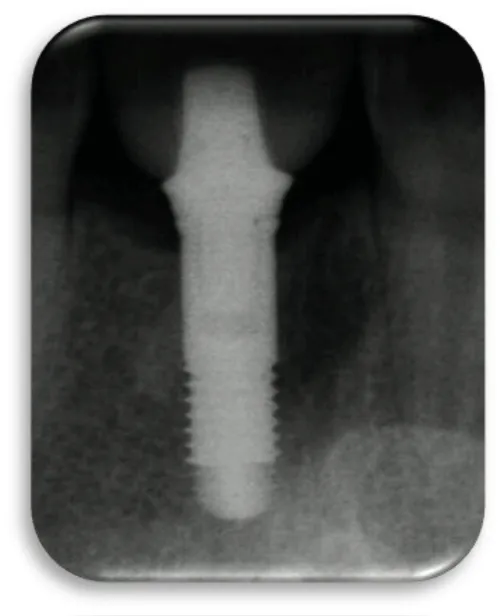

The first patient was at the age of 48 with male gender and generally with good health. There are no contraindications to make oral surgery. The patient is not allergic to any medication. A dental implant was placed 12 months ago (Figures 11,12), the dental implant’s position was 46. The implant was 4.1 mm in diameter and 12 mm in length. The patient has peri-implantitis, a RTG intraoral radiography image was recorded and marginal bone resorption was observed. The depth of the gingival sulcus was 10mm. Dehiscencia was seen in the patient from the buccal side of the implant (Figure 13). The bone defect was closed with a bone graft (Figures 14-16).